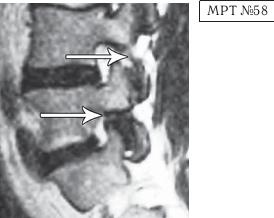

Рассмотрим снимки (стр. 176) для визуального сравнения и более детального понимания течения данного патологического процесса. Гипо- или гиперлордоз является следствием патологических изменений в позвоночнике. Как вы помните, в норме позвоночник человека имеет характерные изгибы. Если же они становятся чрезмерными, то даже несмотря на отсутствие межпозвонковых грыж, протрузий и других патологических изменений, пациенты с гипо- или гиперлордозами часто жалуются на боли как в позвоночнике, так и непосредственно, например, на боли в пояснице с иррадиацией в конечности (по типу корешковых болей). Эти боли, как правило, усиливаются после долгого сидения при подъёме (стартовые боли).

Как правило, причина вышеупомянутых болей при таких патологиях скрывается в дугоотростчатых суставах. Дело в том, что при изменении физиологического лордоза извращается «работа» и дугоотростчатых суставов. В состоянии нормы дугоотростчатые суставы имеют дугообразную форму и расположены во фронтальной, горизонтальной и сагиттальной плоскостях в среднем под углом 45о. При развитии дегенеративнодистрофического процесса в межпозвонковом диске (снижении высоты диска, возникновении сегментарной нестабильности) происходит смещение суставных поверхностей дугоотростчатых суставов по отношению друг к другу, что в свою очередь приводит к уплощению физиологического лордоза и его кифозированию (МРТ № 55) или же формированию гиперлордоза (МРТ № 56). И в том, и в другом случае данные процессы, как правило, сопровождаются сдавлением спинномозговых корешков (что вызывает соответствующие боли). Кроме того, сами дугоотростчатые суставы хорошо иннервированы, поэтому протекание патологических процессов, с участием этих суставов, сопровождается соответствующими болевыми ощущениями.

На МРТ № 55 наблюдается уплощение физиологического лордоза в поясничном отделе позвоночника. На МРТ № 56 наблюдается гиперлордоз в поясничном отделе позвоночника. На МРТ № 57 наблюдаются нарушения конгруэнтности в дугоотростчатых суставах в сегменте LV—SI (указано стрелкой) вследствие гиперлордоза.